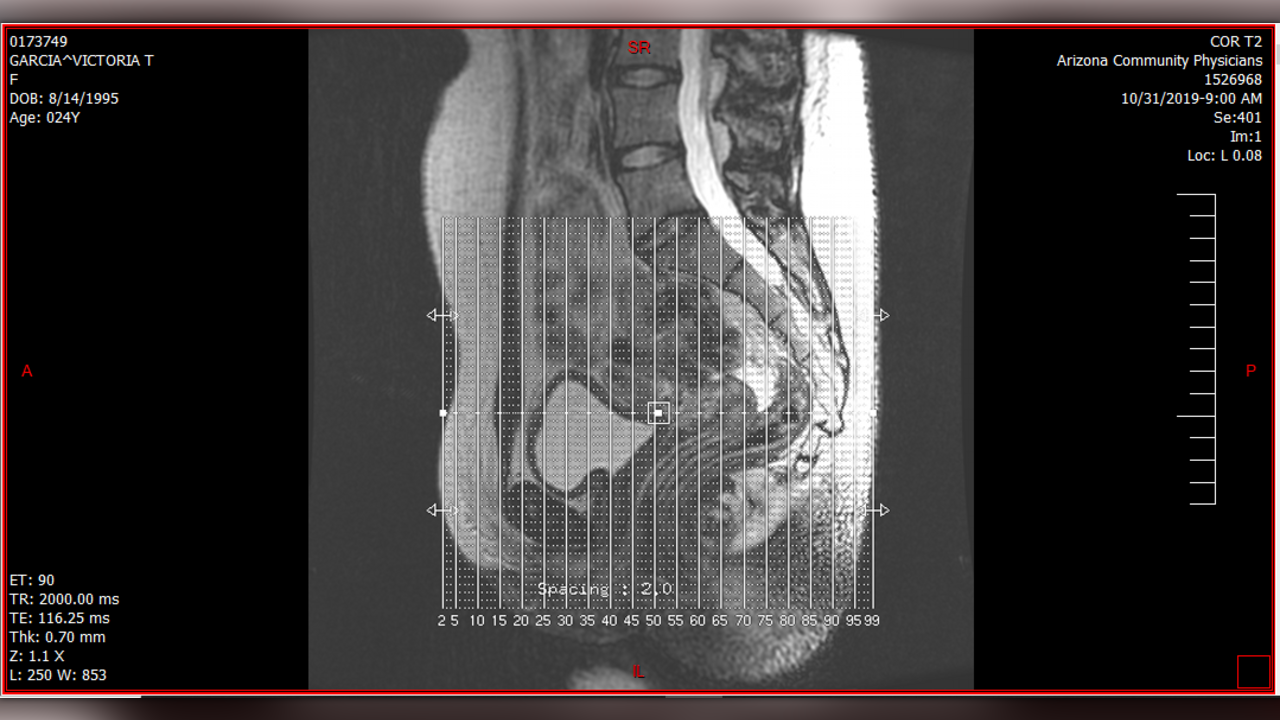

I currently have a cyst on my right ovary that is about 2 cm in size, nearly encapsulating the ovary, and it looks to be growing from the inside of it. With PCOS, there's always a chance that the cyst can burst and if it is growing internally rather than externally, it could take the whole ovary with it. While I can have the cyst surgically removed, it won't prevent future ones from growing. PCOS can be treated with birth control and other medications to prevent future cysts from growing, but because I have had issues with birth control in the past I am more focused on fixing this with surgery.

As far as my liver hemagiomas go, I do now have four confirmed hemangiomas and possibly a fifth that was spotted during my most recent abdominal and pelvic MRIs that I had done on 10/31/2019. Those are still an issue that could also jeopardize my health, but in the meantime our focus is going to be on this cyst.